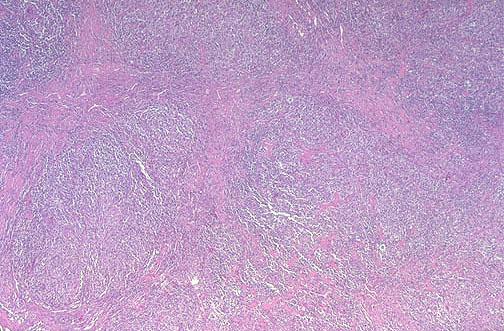

This is Hodgkin lymphoma, nodular sclerosis type. Note the bands of pink collagenous tissue dividing the field in this lymph node.